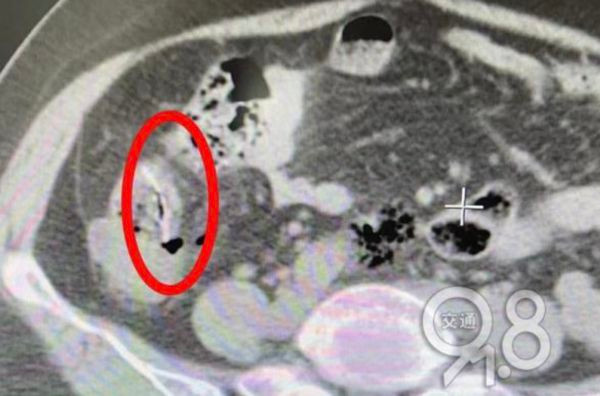

Sau khi khám, bác sĩ phát hiện bạch cầu của người phụ nữ tăng quá mức nghiêm trọng, đây là dấu hiệu cảnh báo bệnh viêm phúc mạc, trong ruột non có những mảnh dị vật, nghi là xương cá mà cô đã nuốt phải vài ngày trước.

Bác sĩ cũng phát hiện trong khoang bụng người phụ nữ có một lượng lớn dịch có mủ, một chiếc gai cá khổng lồ ở hồi tràng đã đâm vào ruột non, lộ ra đầu ruột.